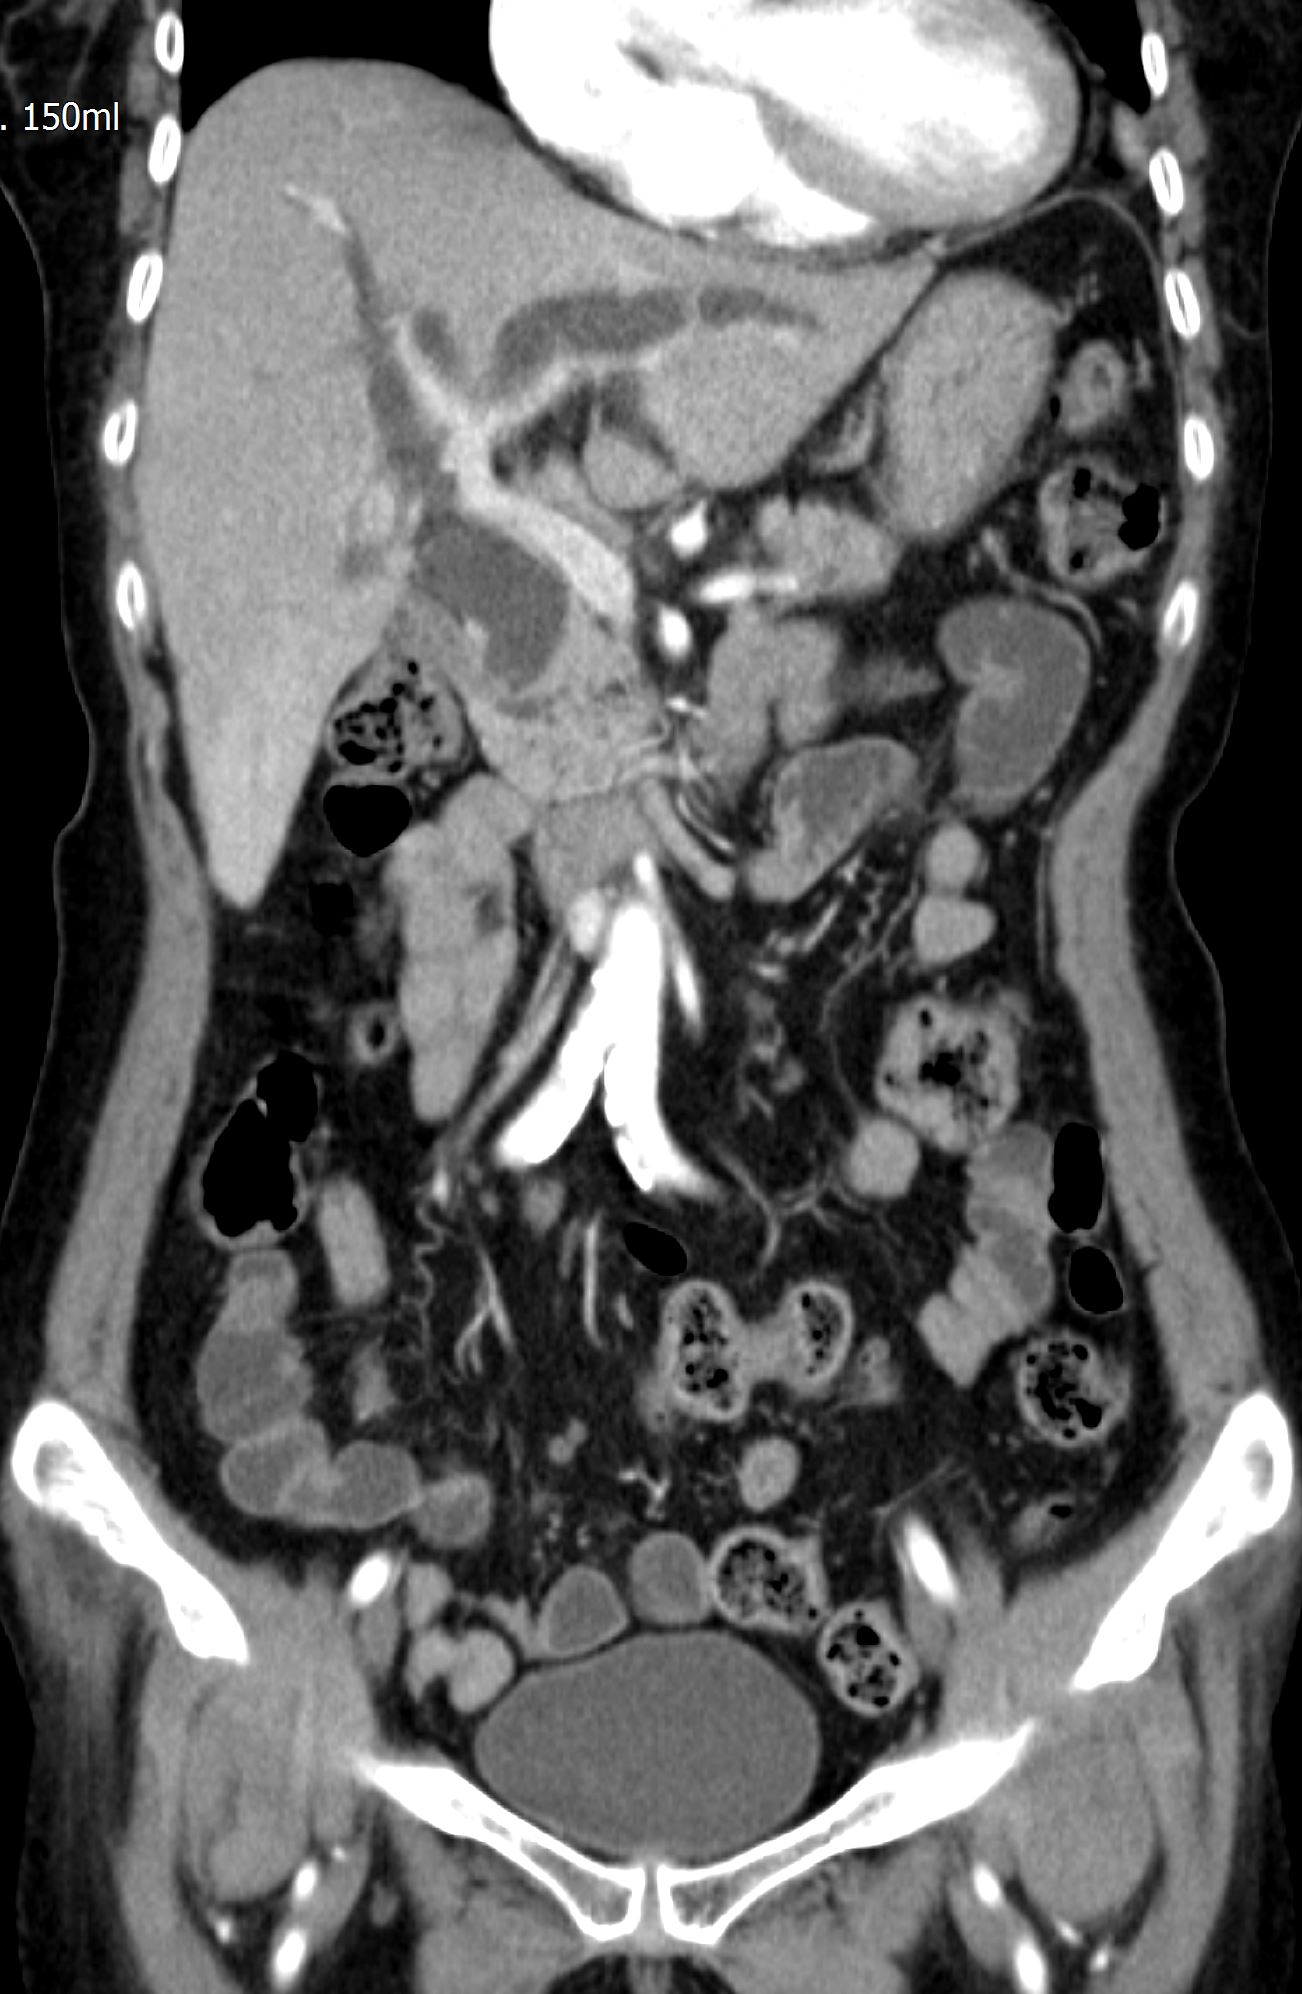

CT에서 보이던 우측 간내담관결석이 보이며, 담관의 확장이 같이 확인됩니다.

CT영상에서는 전혀 안보이던 총수담관 내 결석이 확인됩니다. 그리고, 결석 근처의 총수담관 벽이 불규칙하게 두꺼워져 보입니다.

이처럼 CT에서는 전혀 확인할 수 없었던 간외담관의 결석 및 담관암 의심소견을 초음파 영상에서는 비교적 쉽고 명확하게 확인할 수 있는 사례였습니다. 실제 담관의 확장이 있는 경우 위와 같이 CT에서는 전혀 보이지 않는 병변을 초음파영상에서 확인하는 경우가 꽤 흔합니다. 이러한 경험을 많이 하지 않은 분들이 CT의 유용성을 마치 만능에 가까운 것처럼 착각하는 경우가 있습니다만, 실제로는 이번 사례처럼 그렇지 않습니다.